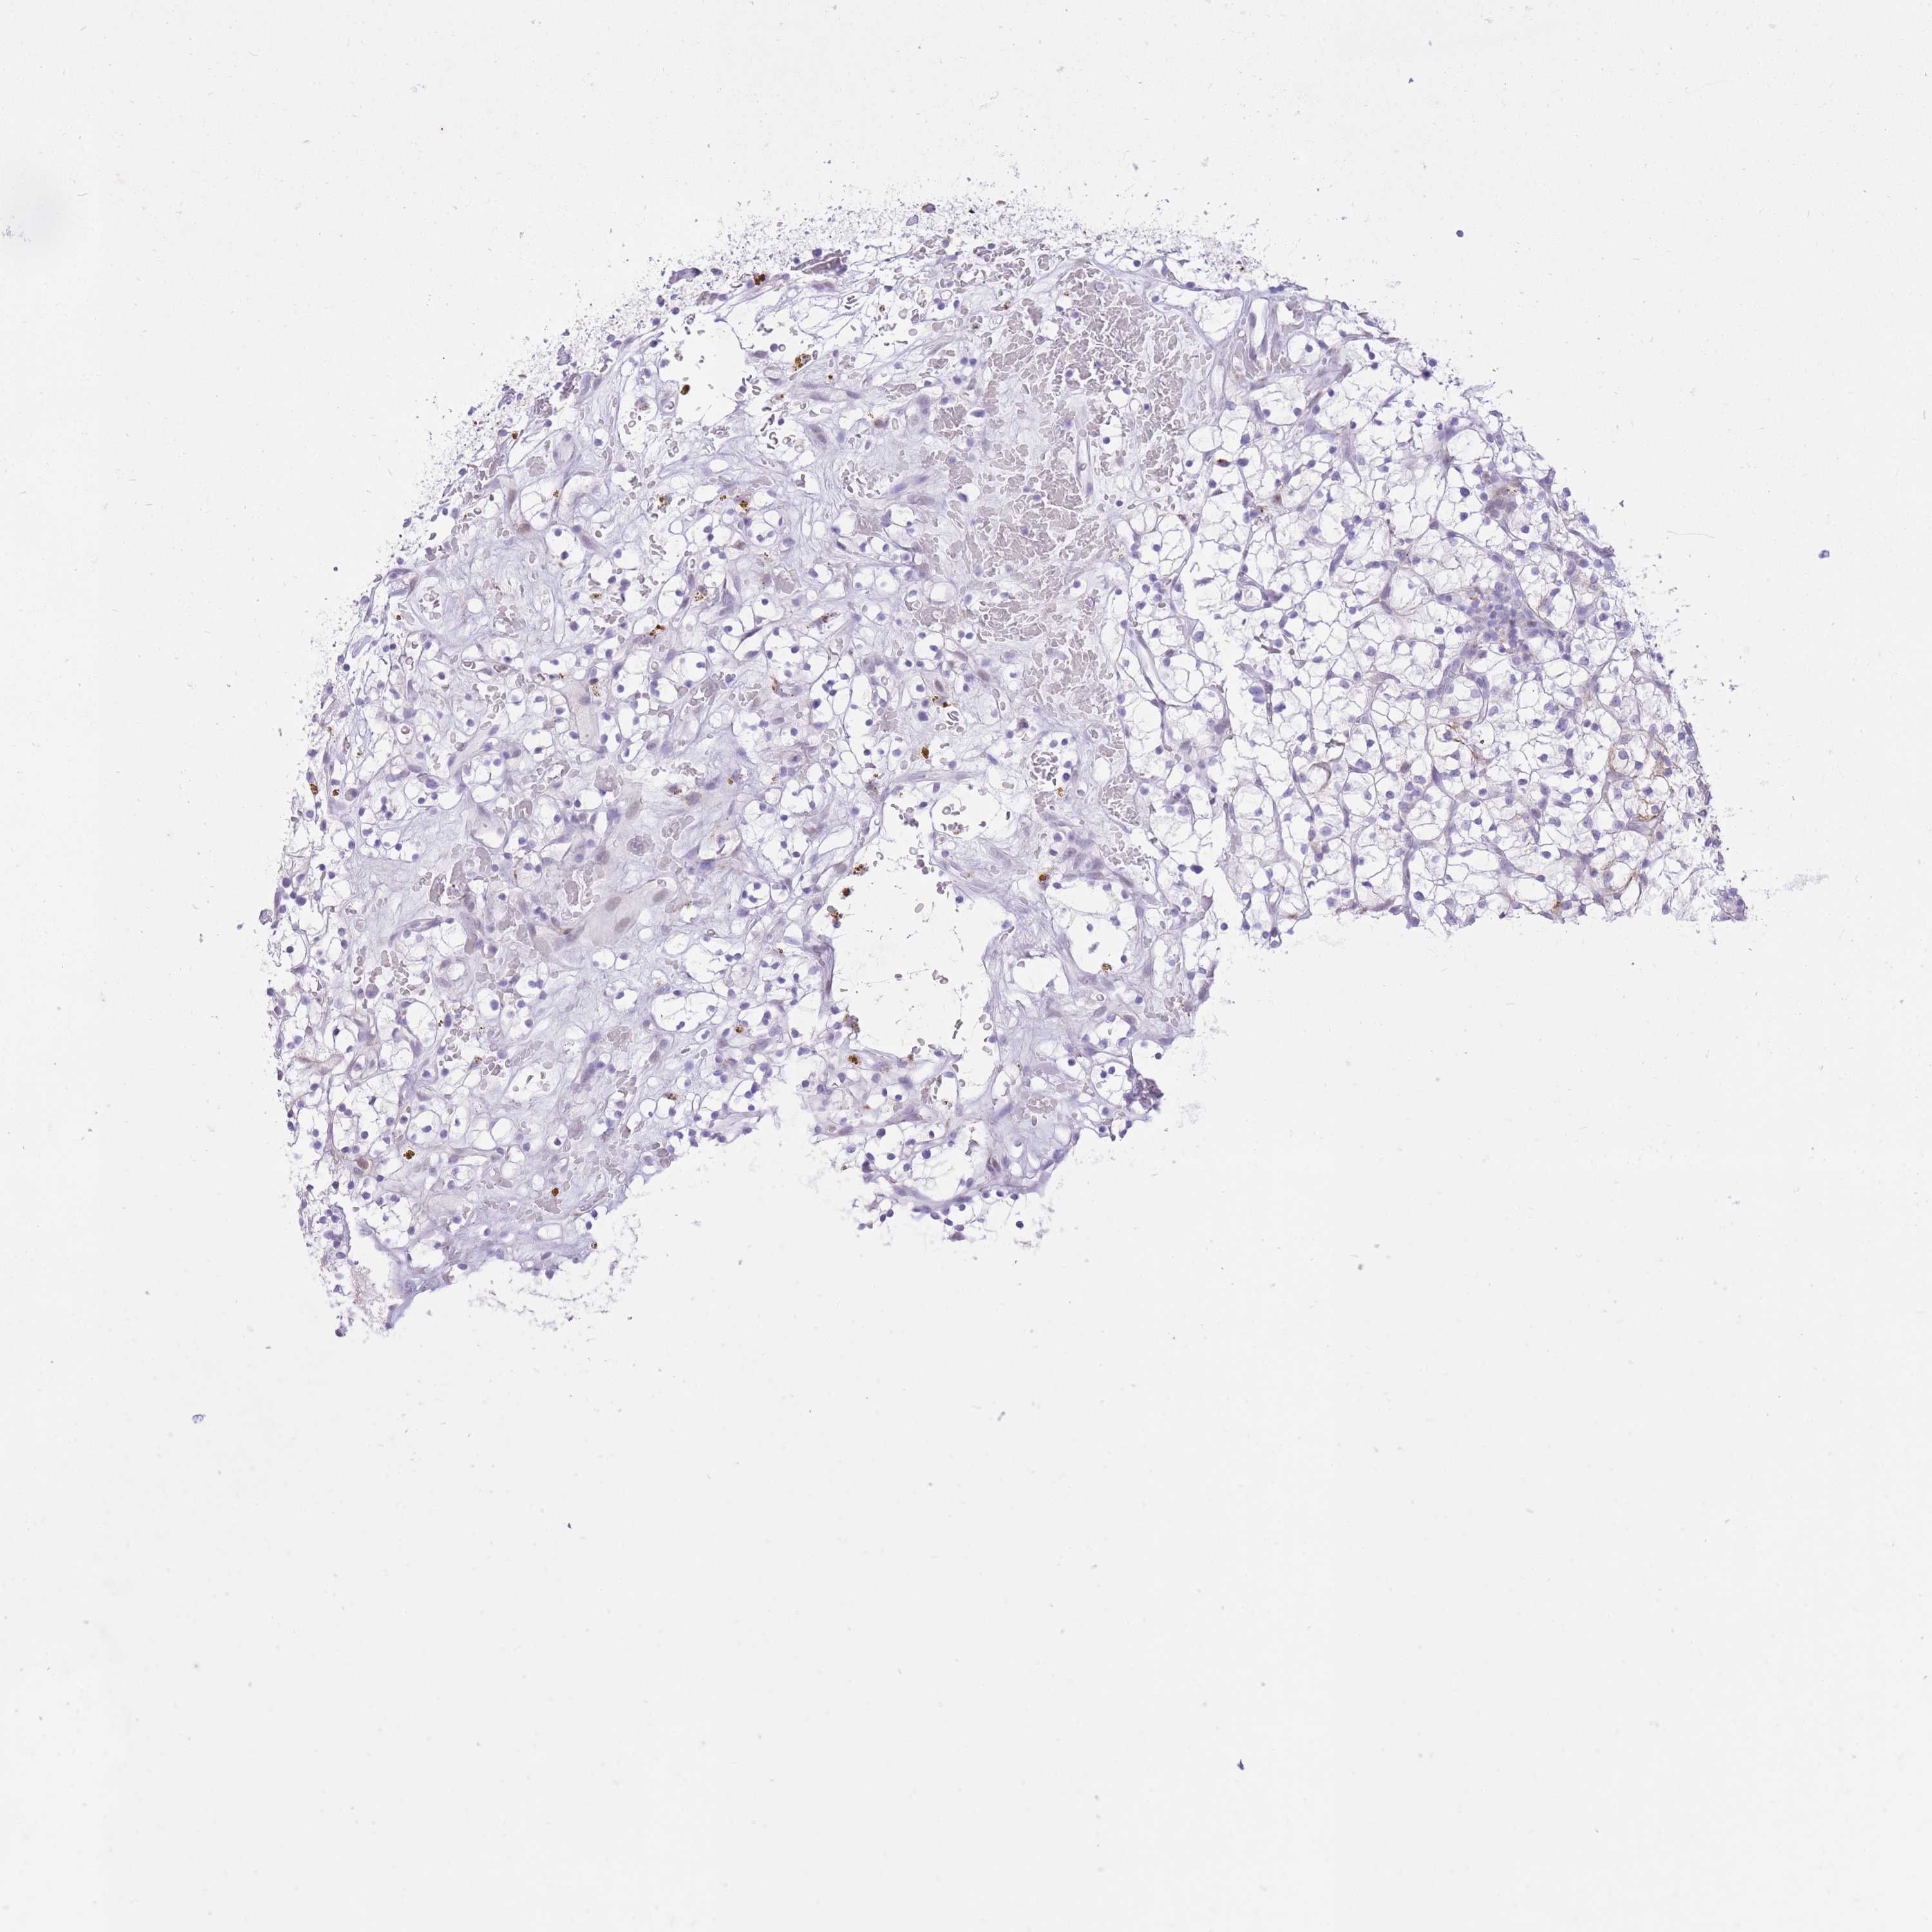

KIDNEY RENAL PAPILLARY CELL CARCINOMA (TCGA) - Interactive survival scatter ploti

The Survival Scatter plot shows the clinical status (i.e. dead or alive) for all individuals in the patient cohort, based on the same data that underlies the corresponding Kaplan-Meier plots. Patients that are alive at last time for follow-up are shown in blue and patients who have died during the study are shown in red.

The x-axis shows the expression levels (FPKM) of the investigated gene in the tumor tissue at the time of diagnosis. The y-axis shows the follow-up time after diagnosis (years). Both axes are complimented with kernel density curves demonstrating the data density over the axes. The top density plot shows the expression levels (FPKM) distribution among dead (red) and alive patients (blue). The right density plot shows the data density of the survived years of dead patients with high and low expression levels respectively, stratified using the cutoff indicated by the vertical dashed line through the Survival Scatter plot. This cutoff is automatically defined based on the FPKM cutoff that minimizes the p-score. The cutoff can be changed by dragging the vertical line or by entering a cutoff value in the square labeled "Current cut-off".

Under the Survival Scatter plot the p-score landscape (black curve; left axis) is shown together with dead median separation (red curve; right axis). Dead median separation is the difference in median mRNA expression between patients who have died with high and low expression, respectively. It is calculated as follows: median FPKM expression of dead patients with high expression - median FPKM expression of dead patients with low expression. This is intended to aid the user in visually exploring custom cutoffs and the associated p-scores and dead median separation.

Individual patient data is displayed and can be filtered by clicking on one or more of the category buttons on the top of the page. Categories describing expression level and patient information include: high, low, alive, dead, female, male and tumor stages. The scale of the x-axis can be toggled between linear and log-scale by clicking on the "x log" button. Mouse-over function shows TCGA ID, patient information and mRNA expression (FPKM) for each patient.

& Survival analysisi

Kaplan-Meier plots summarize results from analysis of correlation between mRNA expression level and patient survival. Patients were divided based on level of expression into one of the two groups "low" (under cut off) or "high" (over cut off). X-axis shows time for survival (years) and y-axis shows the probability of survival, where 1.0 corresponds to 100 percent.

MEIS3 is not prognostic in Kidney Renal Papillary Cell Carcinoma (TCGA)

Best expression cut offi

Based on the FPKM value of each gene, patients were classified into two groups and association between prognosis (survival) and gene expression (FPKM) was examined. The best expression cut-off refers the FPKM value that yields maximal difference with regard to survival between the two groups at the lowest log-rank P-value. Best expression cut-off was selected based on survival analysis .

When clicking on this number, the vertical dashed line indicating cut-off, the interactive survival plot, and the Kaplan-Meier curve will be adjusted to show results based on the best expression cut-off.

: 31.71